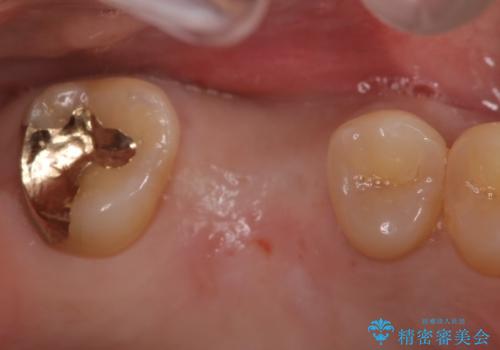

- 歯がないところを何とかしたいとのことで来院されました。

右上奥歯を抜歯された状態でした。

インプラントとブリッジ治療の2通りの治療方法のご提案をさせていただき、インプラント治療をすることとなりました。

インプラントを埋入する際に骨の高さが不足していたので、骨造成も同時に行う計画としました。